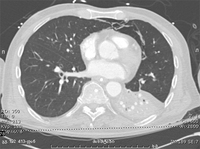

პაციენტის კომპიუტერული ტომოგრაფია, რომელსაც აქვს HAP, გვიჩვენებს ორმხრივ ბაზილარულ დაჩრდილვას.

თანხმობა მიღებულია ლუისვილის უნივერსიტეტში, ლუისვილი, კენტუკი